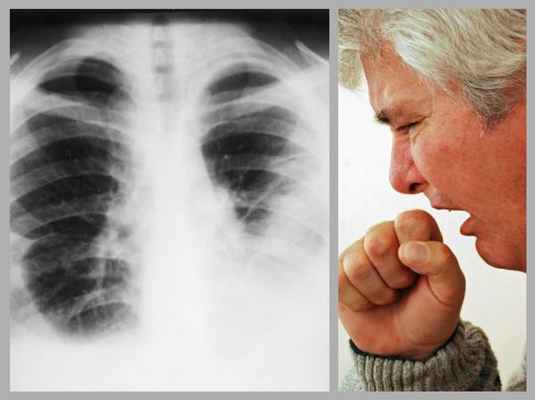

Токсико-аллергический синдром, возникающий вслед за абдоминальным или одновременно с ним, наблюдается у подавляющего большинства больных. Его наиболее частые симптомы - общая слабость, потливость, лихорадка, боли в суставах, уртикарная сыпь, похудание. Тяжесть синдрома соответствует выраженности острых воспалительных изменений в органах дыхания. Длительность этих симптомов - около 1,5-3 месяцев, иногда более. Параллельно токсико-аллергическому развивается и главный синдром - легочный. Симптоматика его малоспецифична и заключается, как правило, в болях в грудной клетке, кашле, одышке. Патоморфогенетической основой этого синдрома кроме описанных изменений легких служит выпотной плеврит и иногда перикардит (фибринозный, серозный, серозно-фибринозный). Различают ранние и поздние (реинвазивные) плевриты, исходом которых являются плевральные сращения.

B клинике личиночного парагонимоза выделяют 4 синдрома: абдоминальный, легочный, токсико-аллергический и неврологический. Больные в первые 4-7 дней жалуются на боли в животе, тошноту, рвоту, поносы, иногда явления «острого живота». Более яркими являются симптомы и признаки поражения легких: жалобы на боли в груди, кашель, одышку, повышение температуры. Характер болей напоминает таковой при крупозной пневмонии, однако рентгенологически инфильтративные изменения не выявляются. Боли часто локализуются в подреберьях, что обусловлено миграцией личинок и повреждением листков плевры и диафрагмы. Они обычно длительные (месяцы) и распространенные (двусторонние). Кашель сухой, надсадный, иногда с прожилками крови в скудной мокроте. Для токсико-аллергического синдрома характерны слабость, потливость, лихорадка, похудание, артрал- гии, крапивница, признаки нарушения функций сердца.

В хронической фазе наиболее повреждены легкие, но могут быть вовлечены и другие органы. Проявления легочной инфекции развиваются медленно и включают хронический кашель, боль в груди, кровохарканье и одышку; клиническая картина напоминает туберкулез Туберкулез (ТБ) Туберкулез (ТБ) является хронической прогрессирующей микобактериальной инфекцией, часто имеющей латентный период после начального инфицирования. Чаще всего ТБ поражает легкие. Симптомы включают. Прочитайте дополнительные сведенияЦеребральные поражения проявляются, как правило, в течение года после начала легочного заболевания. Случаются приступы судорог, афазия, парез и нарушения зрения.

Инкубационный период парагонимоза - от нескольких дней до 2-3 недель, клинические проявления зависят от стадии заболевания. Во время миграции метацеркарий из кишечника в брюшную полость отмечается абдоминальный синдром с явлениями энтерита, острого гепатита, доброкачественного асептического перитонита, симптомами острого живота. Возможно появление кожного зуда. Внедрение личинок трематод в легочную ткань проявляется развитием острого бронхита, бронхопневмонии, геморрагического плеврита.

Острый легочный парагонимоз характеризуется лихорадкой (39-40˚С), одышкой, болью в грудной клетке, кашлем с выделением мокроты с примесью крови (кровохарканьем), в половине случаев - легочным кровотечением. У больных отмечается утомляемость, раздражительность, тахикардия. При остром поражении мозга наблюдаются симптомы менингита, менингоэнцефалита: повышение внутричерепного давления, головокружения, сильная головная боль, судорожные припадки с потерей сознания, сужение полей и снижение остроты зрения. В подкожной жировой клетчатке шеи, грудной клетки и живота могут появляться плотные малоболезненные узлы, содержащие гельминтов и яйца. При внелегочной локализации парагонимоза высока частота осложнений и летальность.